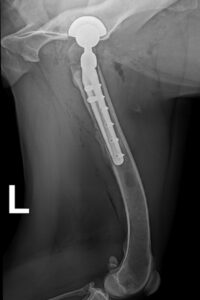

Die Hundehalterin vertraute auf die langjährige Erfahrung von Dr. Klaus Zahn und seinem Team und willigte in die hoch komplizierte Revisionsoperation ein. Allein zwei Stunden brauchte er, um vorsichtig die vorherige Hüftprothese und alle Zementreste aus dem geschwächten Knochen zu entfernen. Schließlich musste die malträtierte Knochenmarkhöhle zur Durchblutungsförderung noch aufgefrischt und körpereigenes Knochenmark eingebracht werden, um eine schnelle Integration der neuen, zementfreien Titanhüfte zu ermöglichen (siehe Röntgenbild 3). Nach der OP hat Neela sehr schnell gute Fortschritte gemacht und lief bereits nach zwei Wochen ohne Schmerzmittel. Nach nun sieben Wochen ist klar, dass die Titanhüfte komplikationslos integriert wurde (siehe Röntgenbild 4 und Video). Dass Neela das Bein wieder deutlich mehr belastet, zeigt sich schon allein daran, dass der Muskelschwund zunehmend weniger wird. Die Halterin ist überglücklich und unendlich dankbar dafür, dass Neela nun schmerzfrei weiterleben kann!